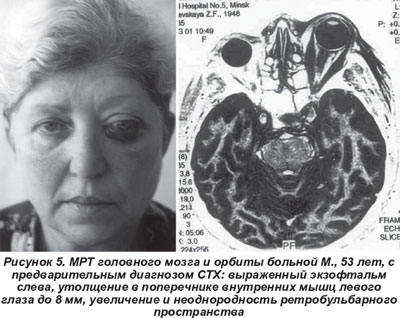

Орбитальный миозит имел место у 4 больных (3 женщины, 1 мужчина, возраст 40-70 лет). Клиническая картина развивалась подостро, отмечались интенсивные боли в орбите, экзофтальм (> 28 мм), выраженный хемоз и диплопия только в одном направлении. Функция щитовидной железы не была нарушена. При МРТ орбиты наблюдалось одностороннее увеличение в объеме внутренних мышц глаза (рис. 5).